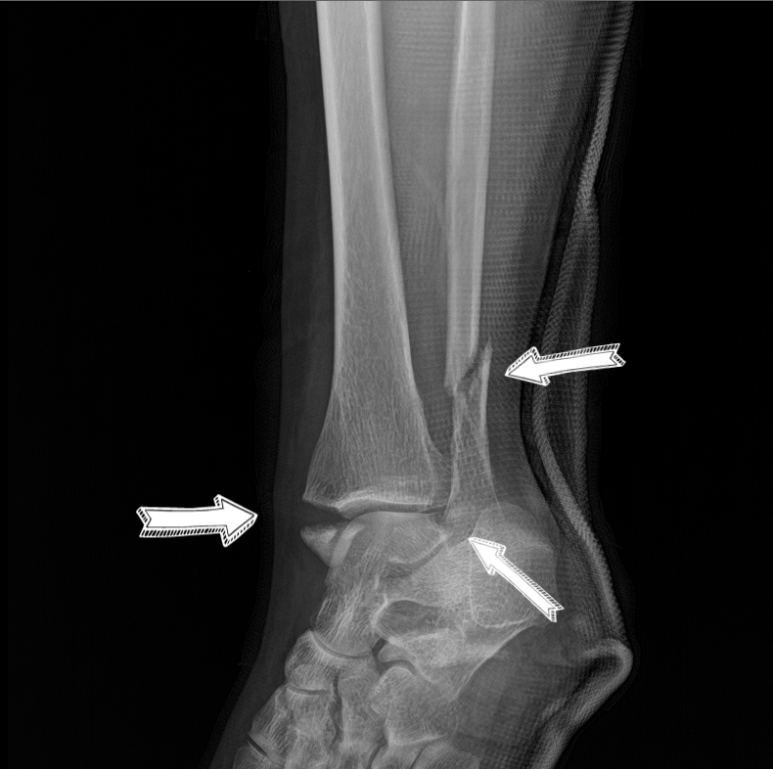

안녕하세요. 오늘 행사는 삼복골절 교통사고 합의 사례입니다.삼복사는 복숭아뼈와 정강이뼈 발목 뒤쪽의 후과를 일컫는 말입니다. 3개의 과(뼈에서 돌출된 부분)를 의미하기 때문에 ‘삼과골절’이라고도 합니다. 덧붙여서 바깥쪽 도골은 경골외과, 안쪽 도골은 비골로 구성됩니다. 위 영상은 전면부이므로 후과골절은 확인이 되지 않습니다. 아래의 X-RAY 영상을 보실 수 있습니다.

피해자는 사고 후 타 병원의 검사 결과 trimal leolar fracture (삼과골절)로 확인되었으며, 수술문제로 상급병원으로 전원 후 관혈적 정복 및 내고정술을 실시하였습니다. 사고로 인한 치료비는 보험사가 지급 보증하므로 걱정하지 마시고, 만약 비급여 치료비를 부담하셨더라도 나중에 영수증 처리가 가능하므로 걱정하지 마시고 치료에만 전념하십시오. 다만 보험사에서 피해자에게 진단서, 수술기록지, 영상판독지, 영상CD 등 다양한 서류를 요구하는 경우가 있는데, 정상적인 지급보증 절차에 필요한 서류는 진단서, 수술기록지 정도이고 영상CD는 추후 후유증 관련 분쟁시 불리할 수 있으므로 추후 제출하는 것이 좋습니다.

왼발관절 삼복사골절 왼발관절부 피부괴사 왼발관절경비인대결합파열 시점은 언제가 좋을까요